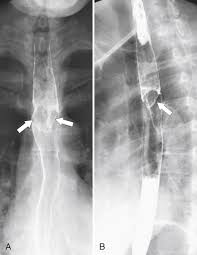

It can arise from a range of causes which include: ( a from levine ms: Canalejo castrillero e, garcía durán f, cabello n, garcía martínez j. Diagnostics and treatment of infectious esophagitis: Animals with mild esophagitis generally have a favorable prognosis.

B from levine ms, woldenberg r, herlinger h, et al.

Clinical guidelines of the russian gastroenterological association. Esophagitis refers to inflammation of the esophagus. Behr j, kreuter m, hoeper mm, wirtz h, klotsche j, koschel d, andreas s, claussen m, grohé c, wilkens h, randerath w, skowasch d, meyer fj, kirschner j. Peptic strictures cause a gradually progressive dysphagia for solid foods. Department of radiology of the loyola university medical center, usa. Epidemiology the actual incidence and prevalence of idiopathic esophagitis of hiv are unknown. Hsv esophagitis has been described in immunocompetent hosts, however, it remains a rare entity. Esophagitis due to herpes simplex virus (hsv) infection1,2. Cobblestone esophagitis (эзофагит со слизистой булыжной мостовой). Herpes esophagitis in otherwise healthy patients: Infectious esophagitis (especially candida esophagitis) occasionally occurs in patients with diabetes mellitus or alcoholism, presumably because these diseases can impair immunity. ( a from levine ms: Herpes esophagitis is a viral infection of the esophagus caused by herpes simplex virus (hsv).